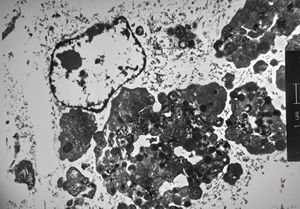

M,6m. | myelinoid inclusions in cerebral neuron - Nieman-Pick disease

M,6m. | myelinoid inclusions in cerebral neuron - Nieman-Pick disease